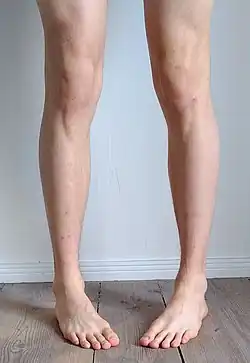

Pigeon toe, also known as in-toeing, is a condition which causes the toes to point inward when walking. It is most common in infants and children under two years of age[1] and, when not the result of simple muscle weakness,[2] normally arises from underlying conditions, such as a twisted shin bone or an excessive anteversion (femoral head is more than 15° from the angle of torsion) resulting in the twisting of the thigh bone when the front part of a person's foot is turned in.